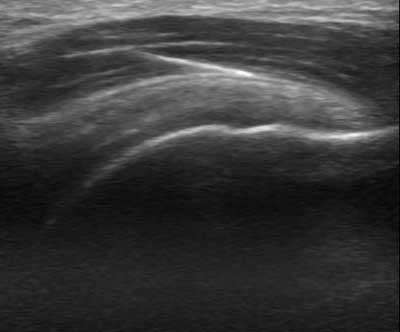

La aplicación de la técnica EPI, consistirá pues en una aplicación de un tipo concreto de electroterapia Galvánica continua con un aguja mediante control eco-guiado para producir una respuesta inflamatoria del tejido degenerado e inducir a su proceso de reparación fisiológico, favoreciendo así la reparación del tejido blando afectado. Ya en 1996, Balcavage et al. observaron que la corriente eléctrica inducida en el tejido a frecuencias bajas (50-60 Hz) tiene un efecto directo sobre la membrana celular.

La técnica EPI® consiste en un primer lugar en realizar una recogida de datos del deportista e historia de su lesión, mediante ecografía músculo-esquelética se realizará un estudio para ver el origen de la lesión, diferenciando ensopatías, tendinopatias, fibrosis y roturas musculares. Creando un protocolo personal con diferentes técnicas y ejercicios dirigidos por un Fisioterapeuta . En muchas ocasiones el ejercicio debe ser corregido mediante vendaje, tipo MaCconnell para la corrección de la alineación rotuliana, y aminorar el dolor.